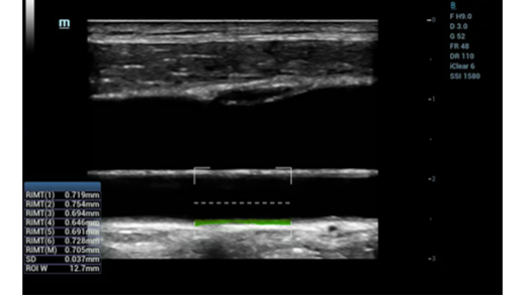

RIMT

- IMT на основе радиочастотных данных и точного измерения IMT в реальном времени

- Ранняя диагностика сердечно-сосудистых заболеваний

- Измеряет радиочастотные данные за 6 сердечных циклов и затем вычисляет максимальное значение для каждого сердечного цикла и среднее значение из 6 максимальных значений

- Высокая точность и автоматическое измерение в реальном времени могут улучшить раннюю диагностику сердечно-сосудистых заболеваний и эффективность последующего лечения